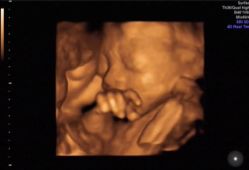

• -郑州万安妇产医院

相册

Miss_Gao 上传于 19-01-08 | 报错